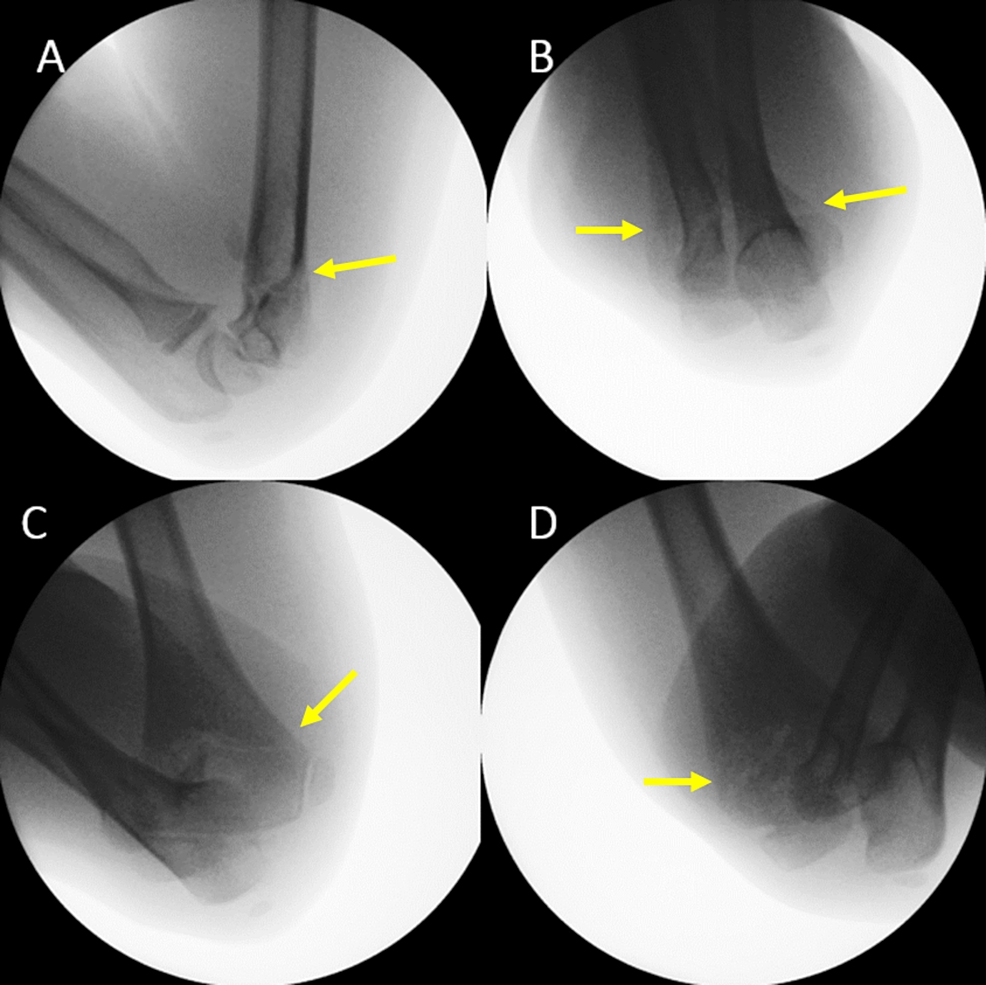

Pediatric Elbow Injury Fat Pad. Grade ii is displaced, but. The objectives of this article are to review. pediatric elbow trauma is challenging because of the complex nature of the growing skeleton. Visible anterior fat pad may be seen in normal patients and should only be. what is the ‘fat pad’ sign? the most important pediatric elbow injury is the supracondylar fracture. Grade i is minimally displaced and needs a cast; any elbow joint distention either hemorrhagic, inflammatory or traumatic gives rise to a positive fat pad sign. If a positive fat pad sign is not present in a child,. Visible posterior fat pad always indicates an elbow effusion. check for raised fat pads: the fat pad sign, first reported in 1954, is a reliable marker for elbow joint effusion and raises. this study provides insight into the current diagnosis and treatment of children with a radiological fat pad sign of the elbow. positive fat pad sign with no visible fracture is managed in a collar and cuff in 90° elbow flexion and virtual fracture clinic follow up.

Grade ii is displaced, but. check for raised fat pads: Grade i is minimally displaced and needs a cast; the most important pediatric elbow injury is the supracondylar fracture. positive fat pad sign with no visible fracture is managed in a collar and cuff in 90° elbow flexion and virtual fracture clinic follow up. any elbow joint distention either hemorrhagic, inflammatory or traumatic gives rise to a positive fat pad sign. what is the ‘fat pad’ sign? the fat pad sign, first reported in 1954, is a reliable marker for elbow joint effusion and raises. If a positive fat pad sign is not present in a child,. Visible anterior fat pad may be seen in normal patients and should only be.

Pediatric Elbow Injury Fat Pad If a positive fat pad sign is not present in a child,. the fat pad sign, first reported in 1954, is a reliable marker for elbow joint effusion and raises. Visible posterior fat pad always indicates an elbow effusion. what is the ‘fat pad’ sign? any elbow joint distention either hemorrhagic, inflammatory or traumatic gives rise to a positive fat pad sign. check for raised fat pads: this study provides insight into the current diagnosis and treatment of children with a radiological fat pad sign of the elbow. Visible anterior fat pad may be seen in normal patients and should only be. the most important pediatric elbow injury is the supracondylar fracture. Grade i is minimally displaced and needs a cast; If a positive fat pad sign is not present in a child,. Grade ii is displaced, but. pediatric elbow trauma is challenging because of the complex nature of the growing skeleton. The objectives of this article are to review. positive fat pad sign with no visible fracture is managed in a collar and cuff in 90° elbow flexion and virtual fracture clinic follow up.